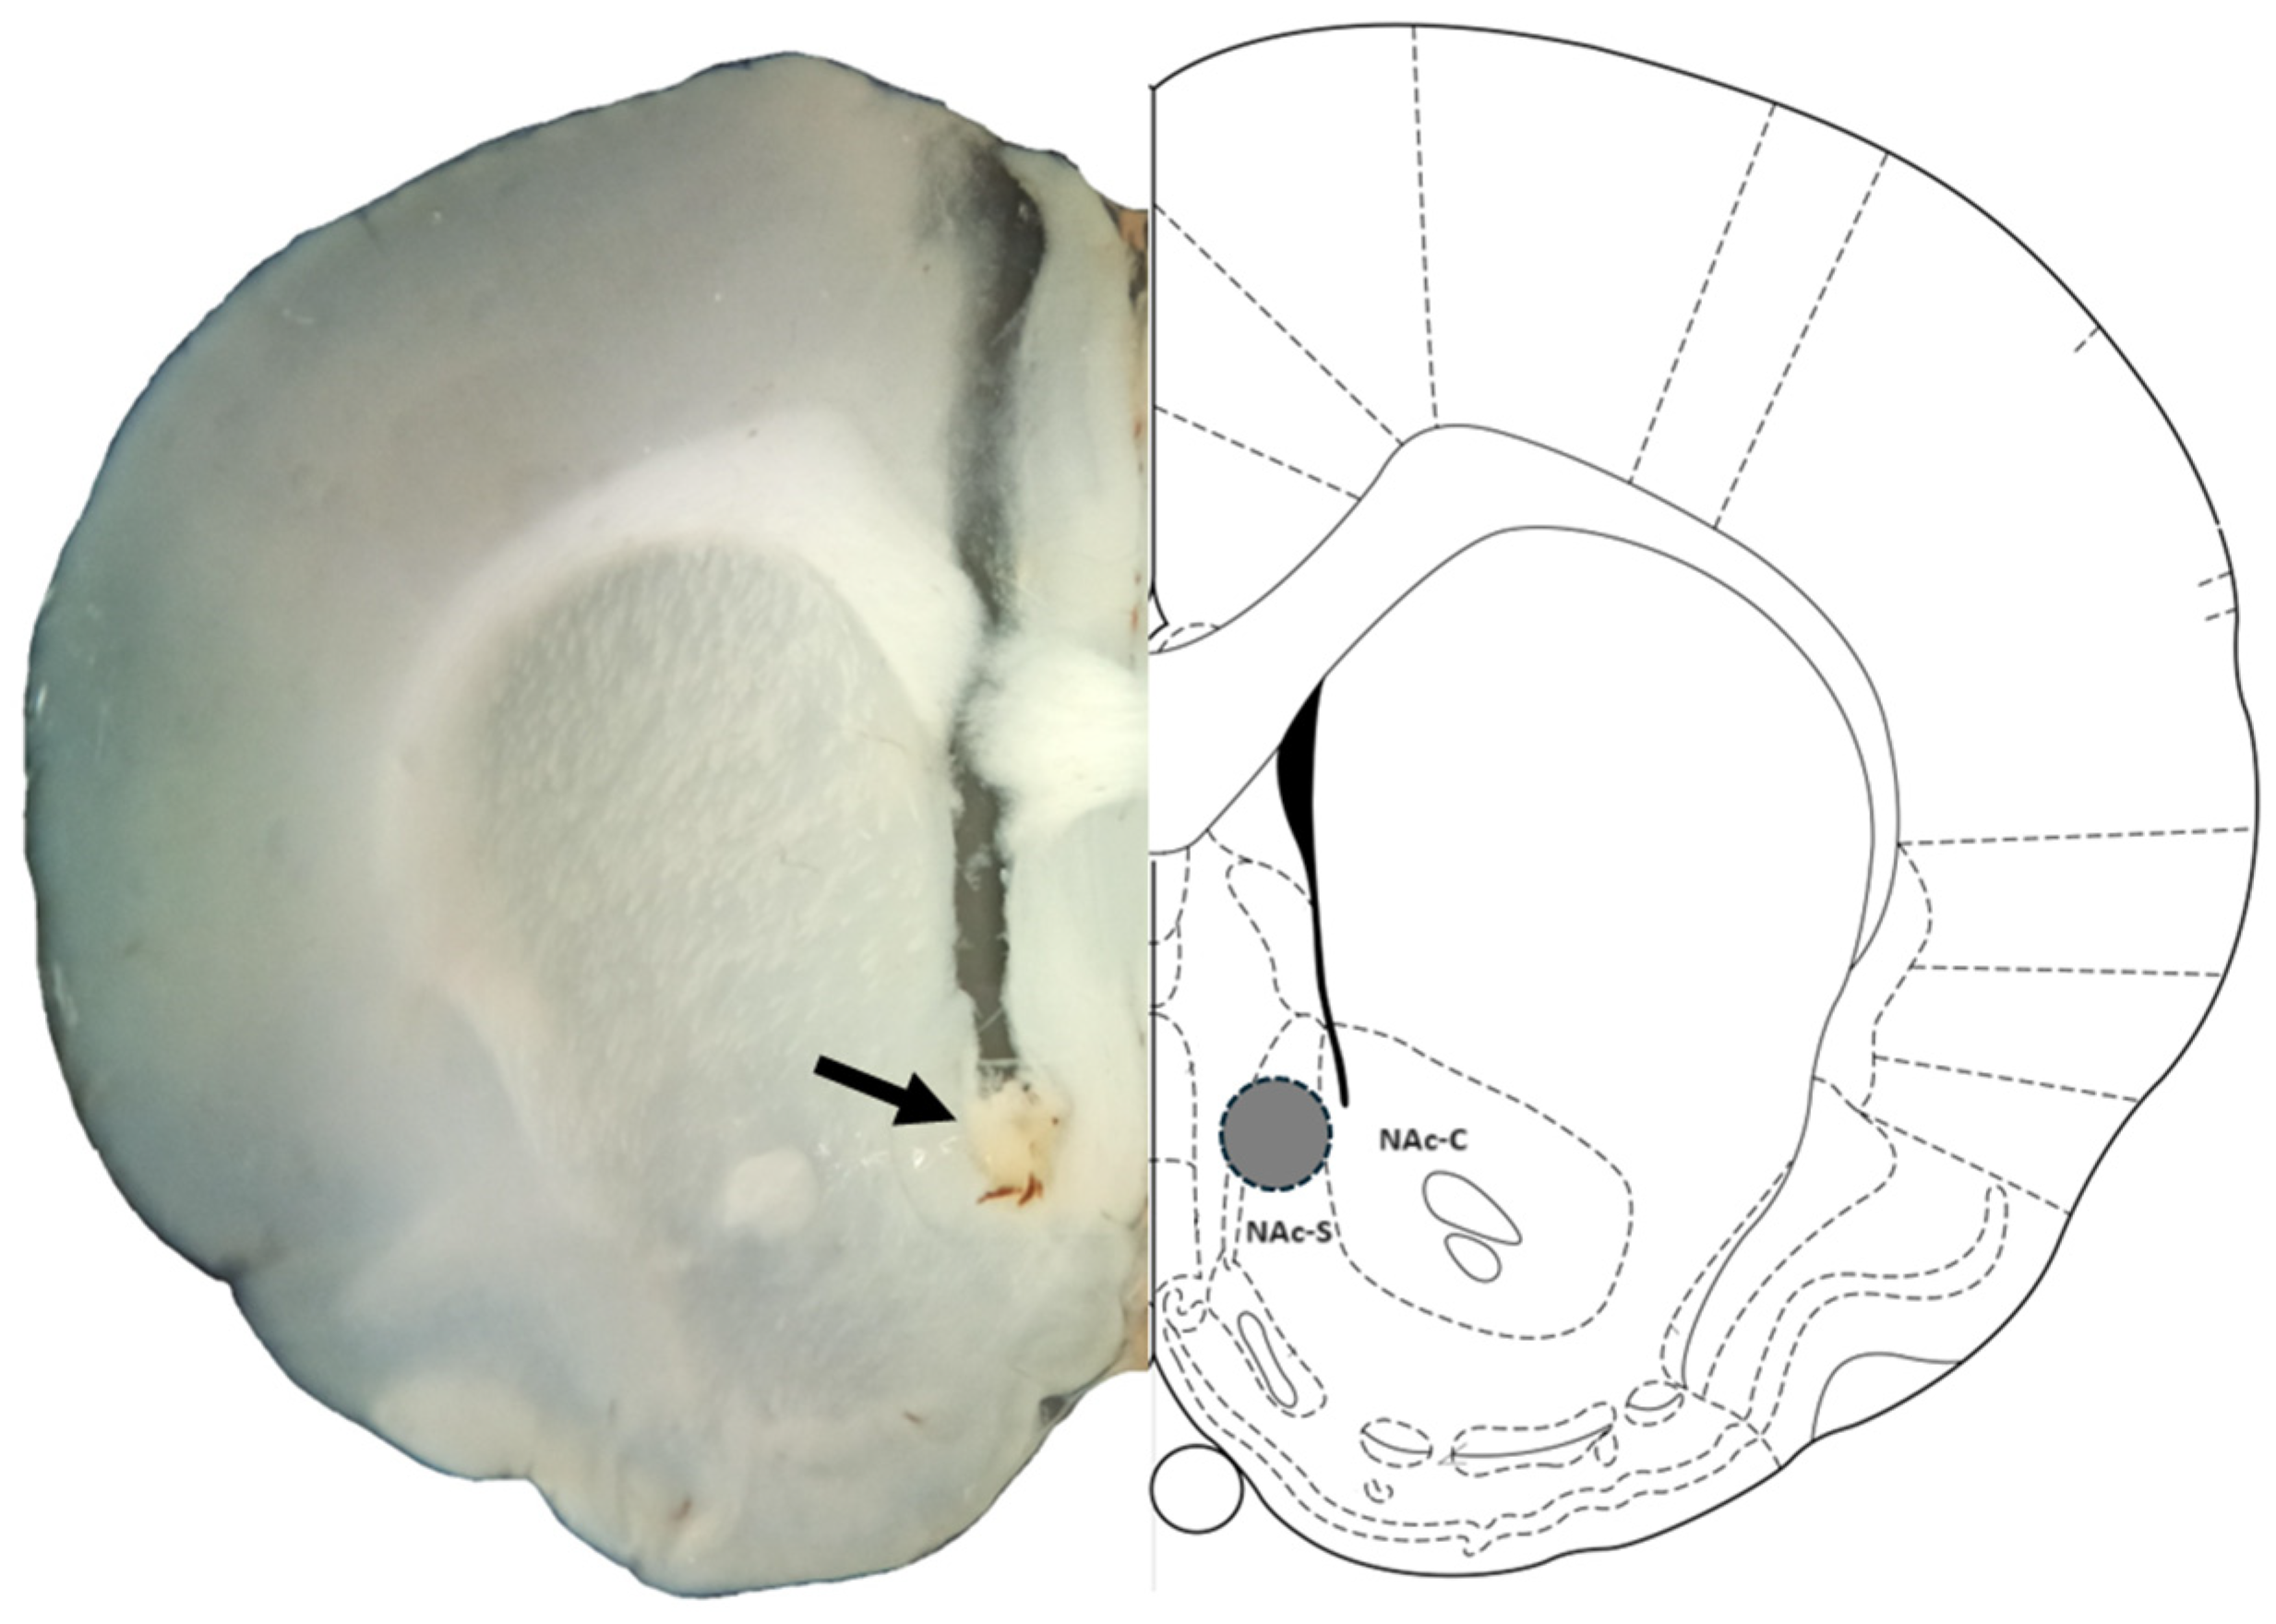

2.8. Histology